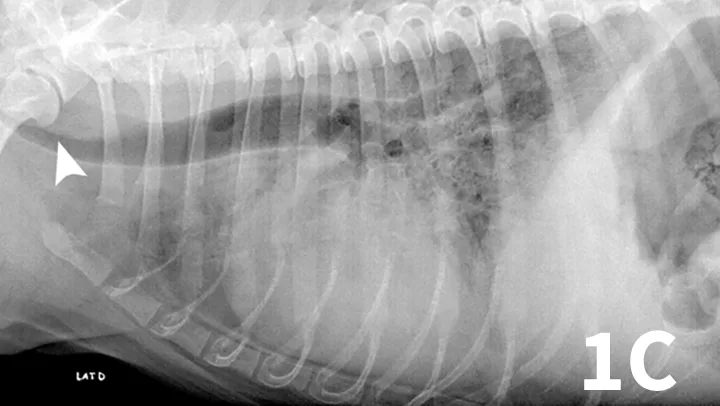

Ventrodorsal (A) and left and right lateral (B, C) thoracic radiographs of a 10-year-old West Highland white terrier showing a redundant tracheal membrane (1B, arrowhead; 1C, arrowhead), a severe generalized bronchointerstitial pattern, and a pleural fissure line (1A, arrow) between right pulmonary lobes.

Serum chemistry panel and CBC results were within range except for alkaline phosphatase (280 IU/L; range, 27-74) and hematocrit (57%; range, 37%-55%). Thoracic radiographs showed a severe bronchointerstitial pattern, right cardiomegaly, and prominent pulmonary artery trunk (Figure 1).